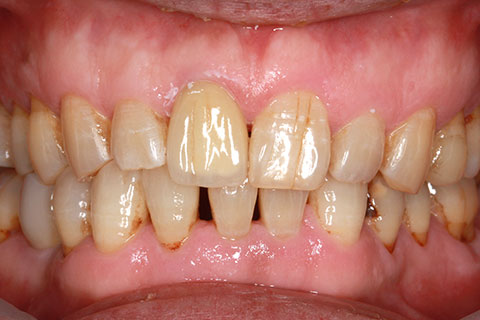

• 症例2

治療前

インプラント埋入時

治療後

年齢・性別

57歳男性

治療期間

3ヶ月

抜歯

なし

治療費

154万円

備考

左上5.6.7 及び左下6.7欠損

治療内容

左上5.6.7と左下6.7欠損部にインプラント埋入

施術の副作用(リスク)

オペによる知覚障害。インプラントによる歯肉炎。インプラント脱落。